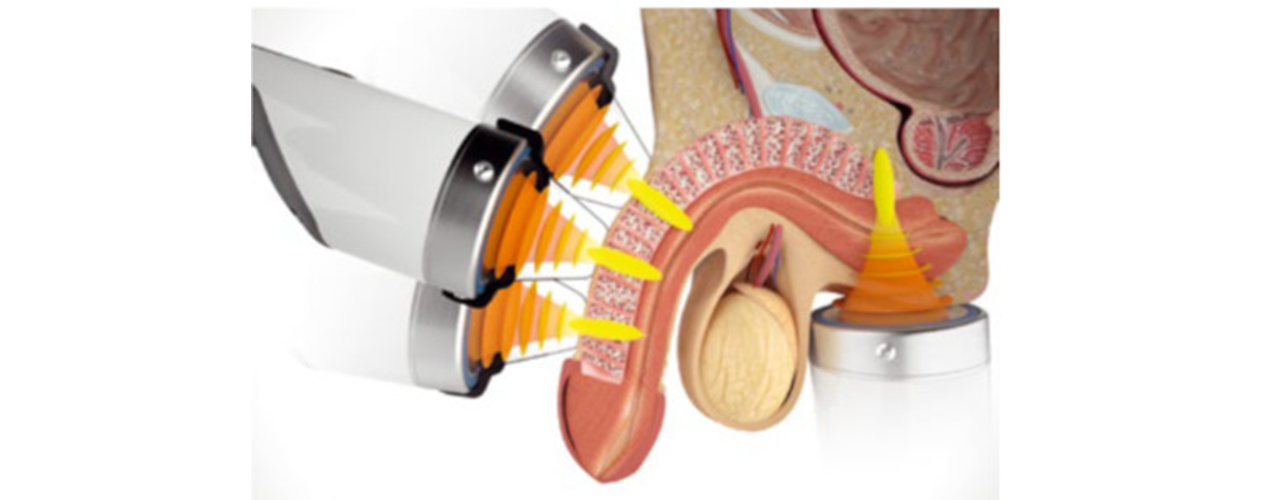

Erectile Dysfunction

Erectile Dysfunction

The focused shockwave causes deep cell stimulation that releases growth factors responsible for tissue regeneration and the initiation of healing processes in the damaged tissues.